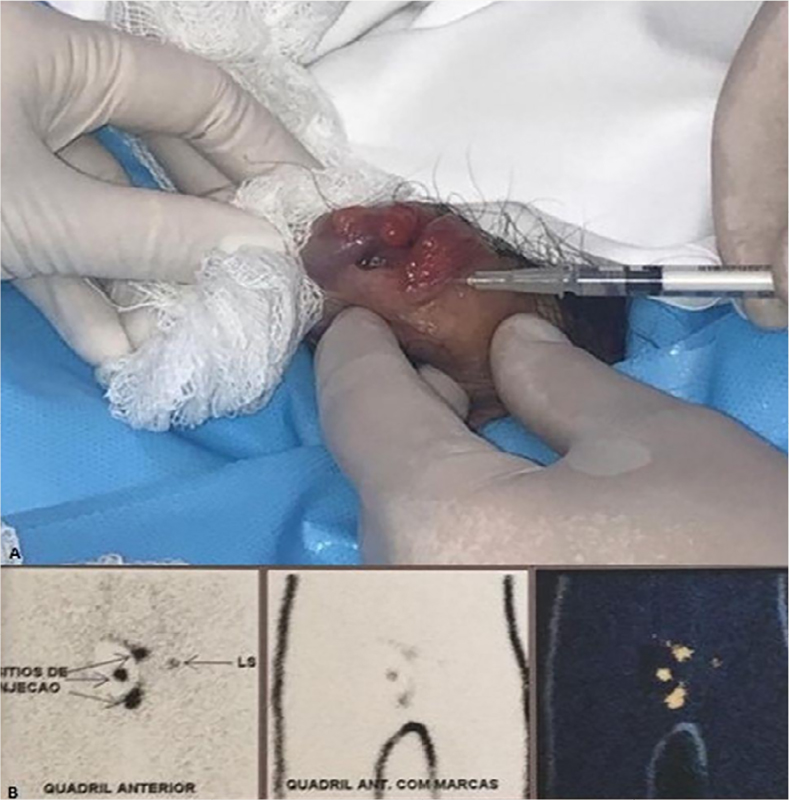

The anatomopathological showed a 7mm thick Clark IV nodular melanoma, with ulceration, without angiolymphatic and perineural invasion. Clinical staging of the disease was performed with chest X-ray, abdominal and pelvis tomography (CT) and cranial magnetic resonance imaging (MRI), with no evidence of regional lymph node enlargement or systemic metastases. Due to the locally advanced clinical stage (T4bN0M0 – ulcerated lesion above 4mm), PET/CT was performed, whose uptake also did not show lymph node or systemic disease. The authors performed partial penectomy and investigation of sentinel lymph node with local technetium injection 12 hours before the procedure (Figure 3), in addition to bilateral inguinal lymphadenectomy at the same surgical time, due to the absence of clinical evidence in the literature that proves the total effectiveness of the sentinel lymph node in the identification of lymph node micrometastasis of penile melanoma, since the lymphatic drainage of the penis is crossed, as it is a midline organ. The margin was subsequently enlarged by 2cm due to impairment (Figure 4).

Figure 3 A. Technetium injection 12 hours before the surgical procedure in triangulated points, close to the primary lesion on the penis; B. Lymphoscintigraphy showed uptake of the radiopharmaceutical in the left inguinal lymph node chain.